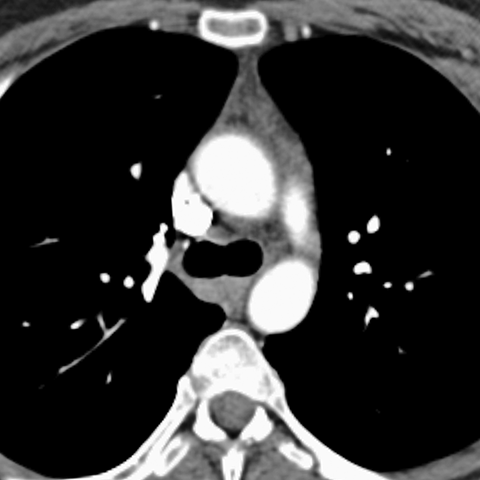

Normal Thymus, 20 Year Old (Chest CT) [2 of 3]